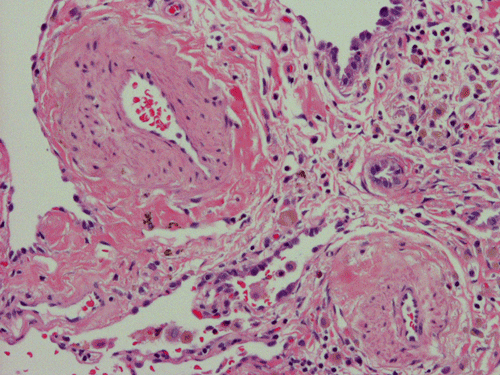

At scanning magnification (Panel A), the lung parenchyma is replaced by some coalescing fibrous nodules. The degree of involvement is variable at different fragments (Panel B and C). In the less affected areas, there are some fibrotic thickening of the septa (Panel C). In some areas, the changes are minimal and the pleural appear to be uninvolved (Panel D and E). In low to medium magnifications, these nodules of fibrosis contains a large number of hemosiderin laden macrophages (Panel F and G) admixed with fibrous tissue. The diagnostic tissue, however, is present in areas with increased cellularity. In these areas, there is a background of cells with a moderate amount of cytoplasm and bland nuclei. Some of these nuclei have kidney shape (arrow in Panel H). In some areas, many of the nuclei have a deep nuclear groove that resemble a coffee bean (arrow in Panel I). In the third type of areas, the nuclear grooving is not distinct (Panel J). Prominent eosinophilic infiltrations are almost always present. Immunohistochemistry on CD1a revealed many positive cells (Panel L). Also present in the specimen are multiple small blood vessels with thickened intima (Panel K). A Movat pentachrome stain demonstrates an internal elastic layer in these vessels and confirms that these are arteries (Panel M and N).

Pathologically, PLCH can be broadly divided into an early or cellular stage and a late or fibrotic stage. Demonstration of LCs is of critical importance for a correct diagnosis. The morphology of LCs is similar to LCH in other organs. LCs are characterized by a deep nuclear groove which lead to “coffee bean-shaped” or “kidney-shaped” nuclei. In most cases, the level of atypia and pleomorphism is low. A moderate amount of amphophilic to weakly eosinophilic cytoplasm is present. The cytoplasmic membrane is indistinct. Eosinophils and chronic inflammatory cells, varying from scant to abundant, are present. Except for a scant frankly pleomorphic cases, the level of pleomorphism and atypia is minimal to low. Eosinophilic abscesses with central necrosis may be present. Immunohistochemically, LCs are similar to their normal counter parts and are positive for CD1a and S100. At the ultrastructural level, Birbeck granules can be demonstrated. For most cases, the diagnosis can be established by histopathologic criteria but these additional features help to confirm the diagnosis.

In the early stage of PLCH, there are interstitial infiltrates composed of LCs, lymphocytes, macrophages, eosinophils, plasma cells and fibroblasts 4. The infiltrates enlarge to form nodules centered on the small airways. Brown pigmented macrophages (smokers macrophages) are present in and around the nodules. Eosinophils tend to localize at the innermost layer of the nodules, where LCs can be most easily found in the thickened interstitium. Associated patchy interstitial and airspace organization or respiratory bronchiolitis may be present. Other smoking related changes are also common. Cavitation often occurs within the nodules which represents either an airway remenant or de novo cavitation as the inflammatory infiltrate enlarges. There is centripetal replacement of the nodules by fibroblasts which produce the classic stellate lesions of PLCH. As the disease progresses, the number of nodules, cavitary granulomas and fibrotic scars increase in number.